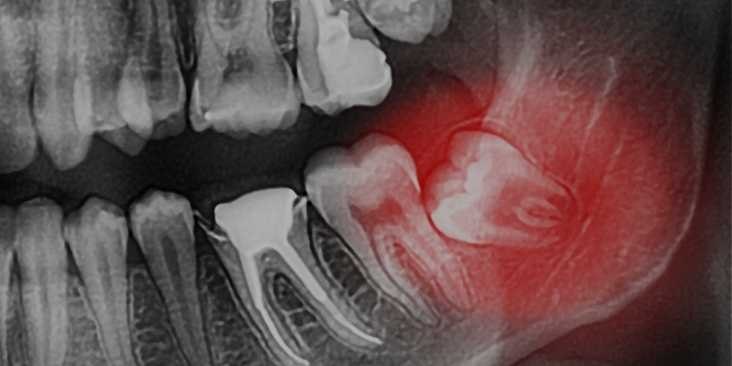

Экстракция зуба

Принцип работы пьезохирургического аппарата основан на ультразвуковых колебаниях в диапазоне от 28 000 до 36 000 Гц. При экстракции зуба микровибрации этой частоты бережно отделяют зуб от окружающих тканей и кости. Никаких выкручивающих движений щипцами и элеватором! Зуб извлекается без травматизации альвеолярной лунки и нервно-сосудистого пучка, без повреждения корней соседних зубов.

Самое важное — при удалении зуба по технологии пьезохирургии пациент сохраняет альвеолярный гребень. Это позволяет обойтись без остеопластики и длительной реабилитации, если на место удаленного зуба планируется устанавливать имплантат.